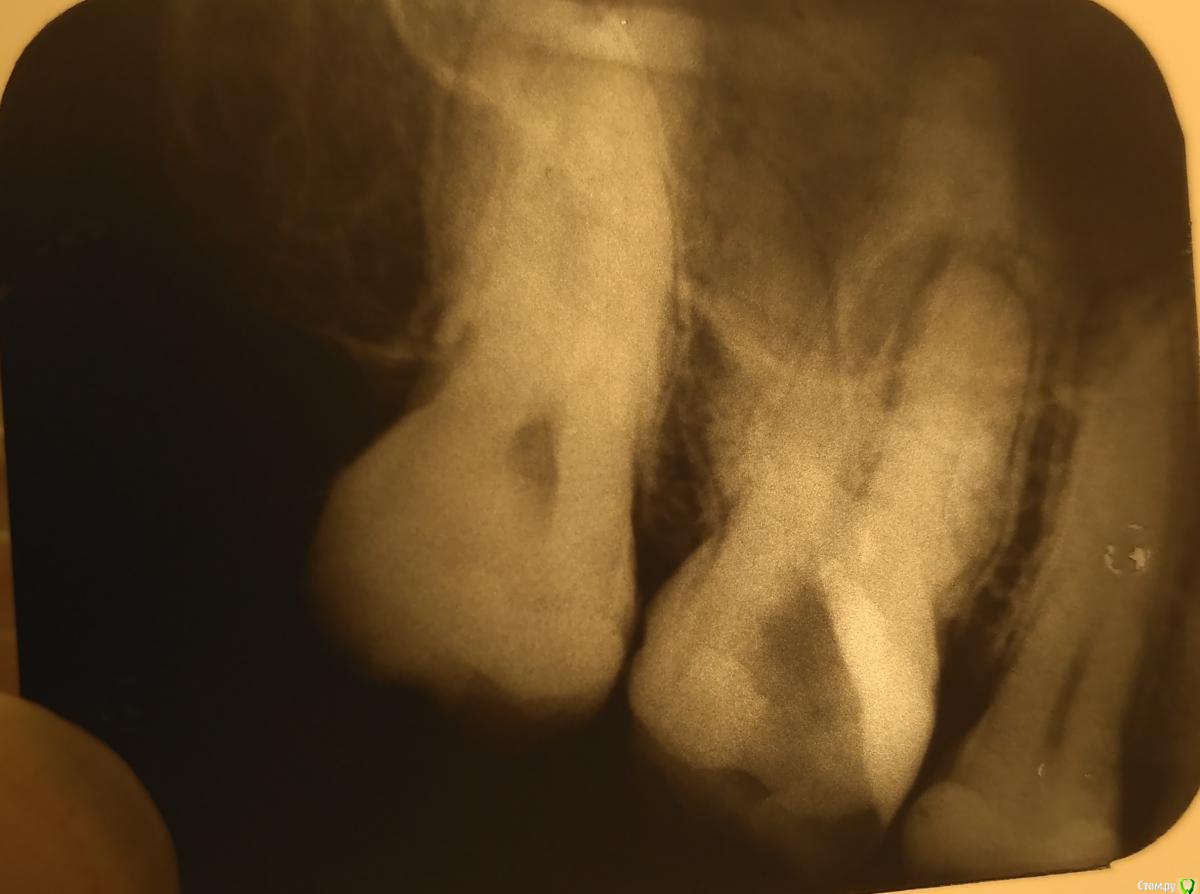

Киста верхней 6-ки (левая сторона).

Мучали сильнейшие боли, опухла щека, свищ. Ставили дренаж, врач вскрыла зуб, каналы были прочищены, заложено лекарство, пила антибиотики. Во время лечения оставались достаточно сильные боли. Через пару недель, когда уже стояла временная пломба, наконец стало легче.

Прикладываю снимки - с начала лечения до финального прицельного снимка, а также ОТПГ, а также результаты общего анализа крови.

Врач говорит, что по снимкам всё хорошо, но какой же тогда выход?